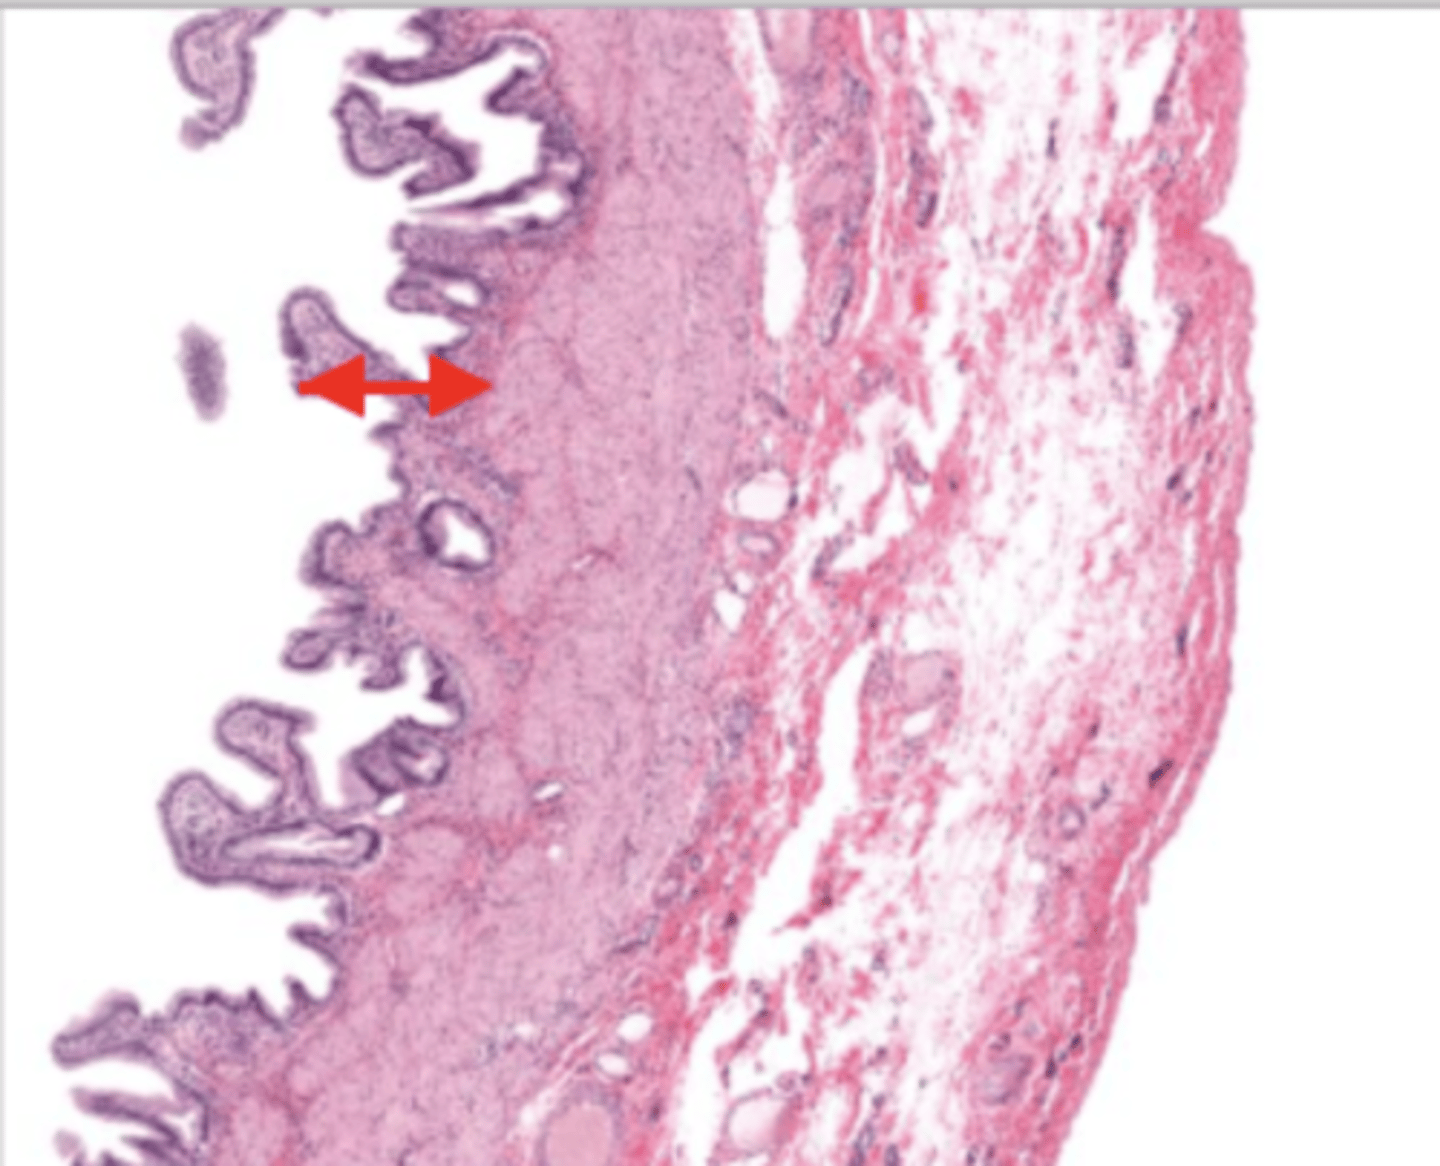

gallbladder (histology)

gallbladder

this tissue's wall structures/layers are different than the rest of the organs

simple columnar epithelium

what kind of epithelium lines the mucosa of the gallbladder

lumen (gallbladder)

mucosa (gallbladder)

mucosal epithelium (gallbladder)

lamina propria (gallbladder)

muscularis mucosa and submucosa

gallbladder tissue does not have _______ and ______

muscularis externa (gallbladder)

serosa/adventitia (gallbladder)